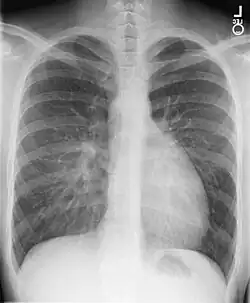

- Chest X-ray: On chest X-ray (CXR), transposition of the great vessels typically shows a cardio-mediastinal silhouette appearing as an "egg on a string ", in which the enlarged heart represents an egg on its side and the narrowed, atrophic thymus of the superior mediastinum represents the string.[4]